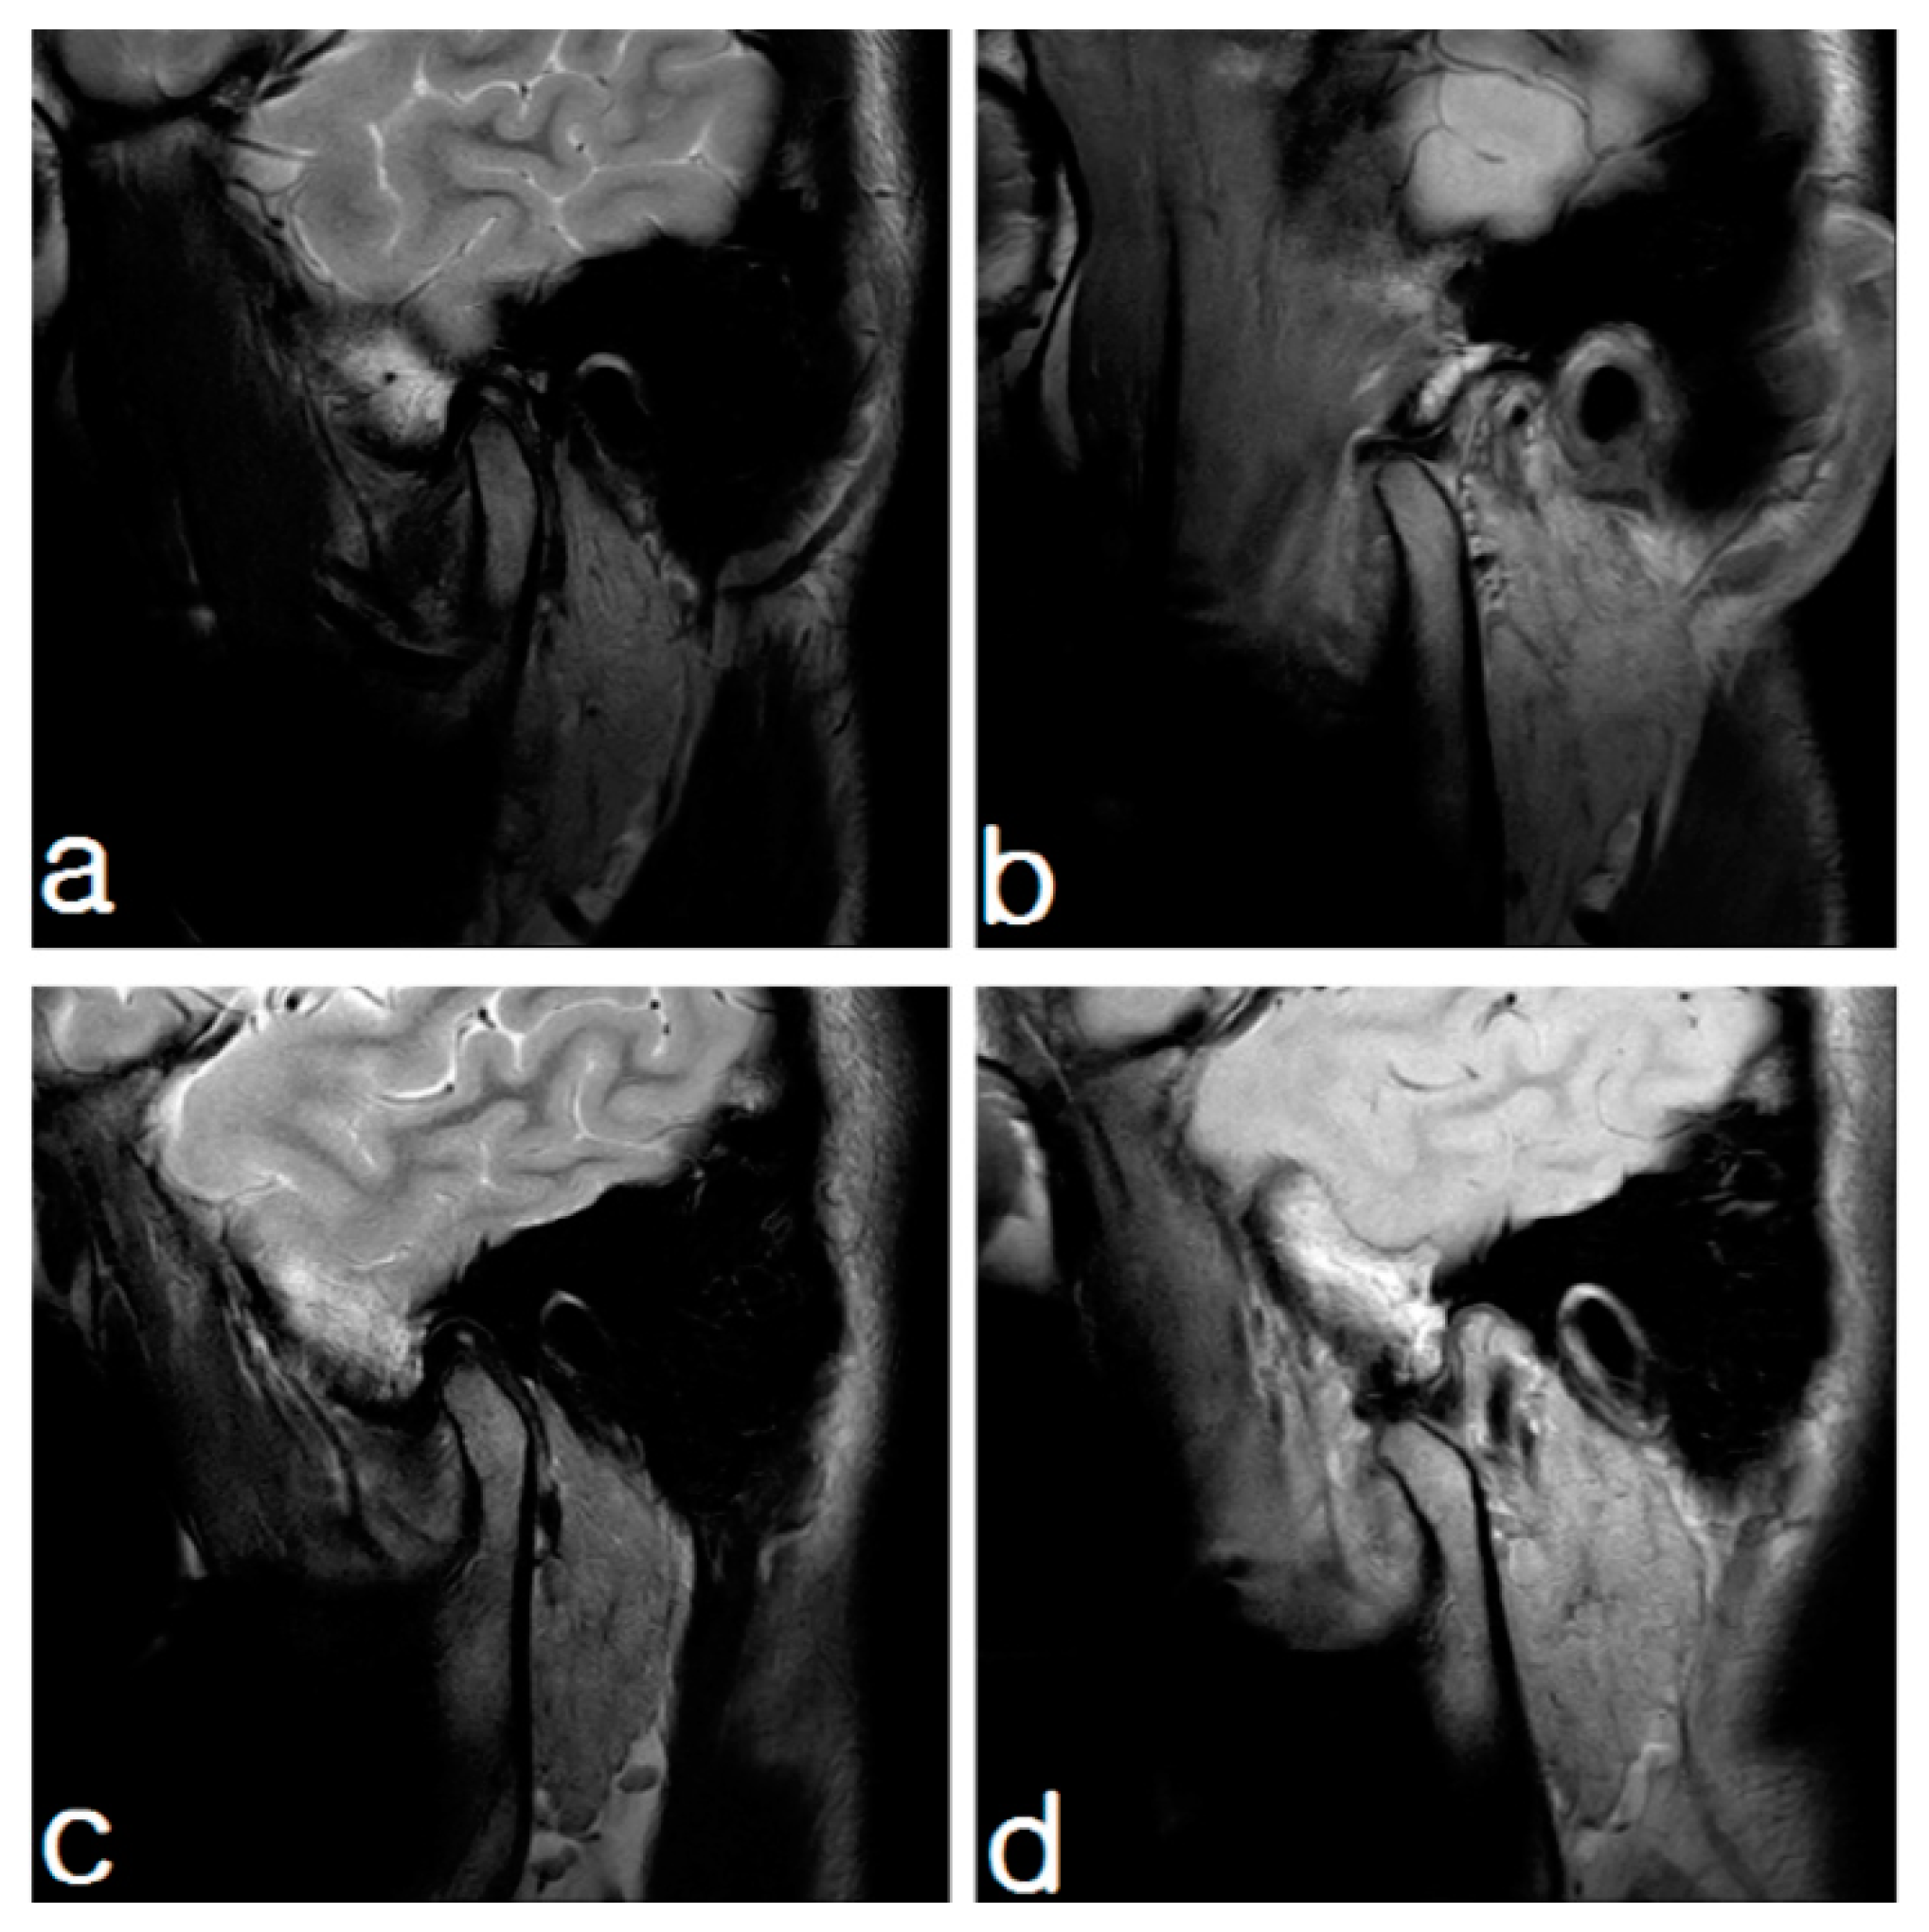

2.1.2. Imaging

2.2.2. Imaging